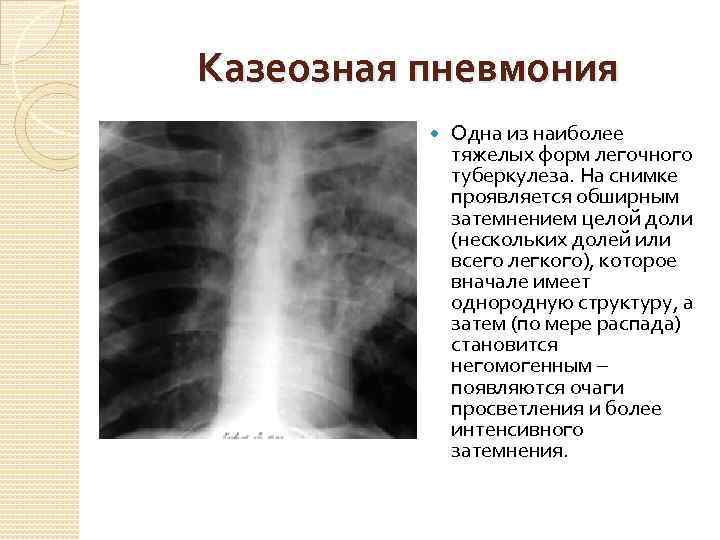

Симптомы и признаки туберкулеза: как распознать заболевание

Раздел: Визуальные уроки